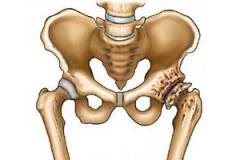

Это вызывает неравномерное распределение нагрузки во время движений. Часть суставного хряща, испытывающая повышенное давление, начинает изменяться анатомически и функционально. В области хронического повышения давления развиваются склеротические процессы, и в хряще появляются трещины. Суставные поверхности костей становятся неровными и шероховатыми.

Такой процесс приводит к компенсаторным реакциям. Сначала наблюдается разрастание хрящевой ткани в зоне повреждения и вокруг нее. Если нагрузка продолжается, хрящевая ткань начинает погибать, и на ее месте формируется костная. Костные разрастания могут возникать не только в области повреждения, но и вокруг нее, образуя остеофиты — костные выросты, направленные в полость сустава.

При прогрессировании коксартроза страдают и другие компоненты сустава. В суставной капсуле образуется фиброзная ткань, которая уплотняется и теряет подвижность. Внутрисуставные связки становятся менее прочными и могут спаиваться с синовиальной оболочкой, где также появляются очаги фиброза. Если лечение не начнется вовремя, конечным этапом станет фиброзирование и сращение внутрисуставных компонентов, выраженное разрастание остеофитов, сближение суставных поверхностей костей и сужение суставной щели, что приведет к значительному ограничению или полной утрате подвижности в суставе.